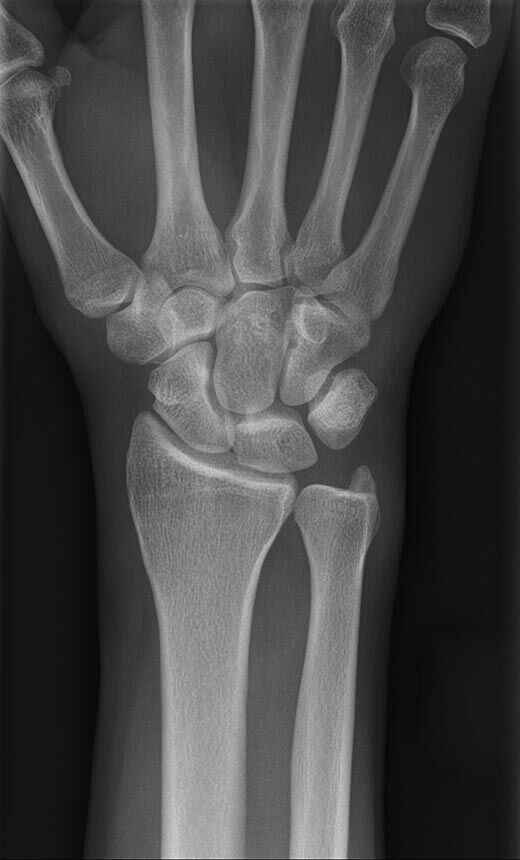

Röntgen Knochen

Röntgenaufnahme einer Hand

• Fraktur

• Arthrose

• Rheumatische Gelenkerkrankungen

• Degenerative Veränderungen der Wirbelsäule

• Knochentumor

• Osteoporose

• Therapiekontrolle nach OP am Skelettsystem

• Vollautomatische Erstellung von Ganzbein- und Ganzwirbelsäulenaufnahmen